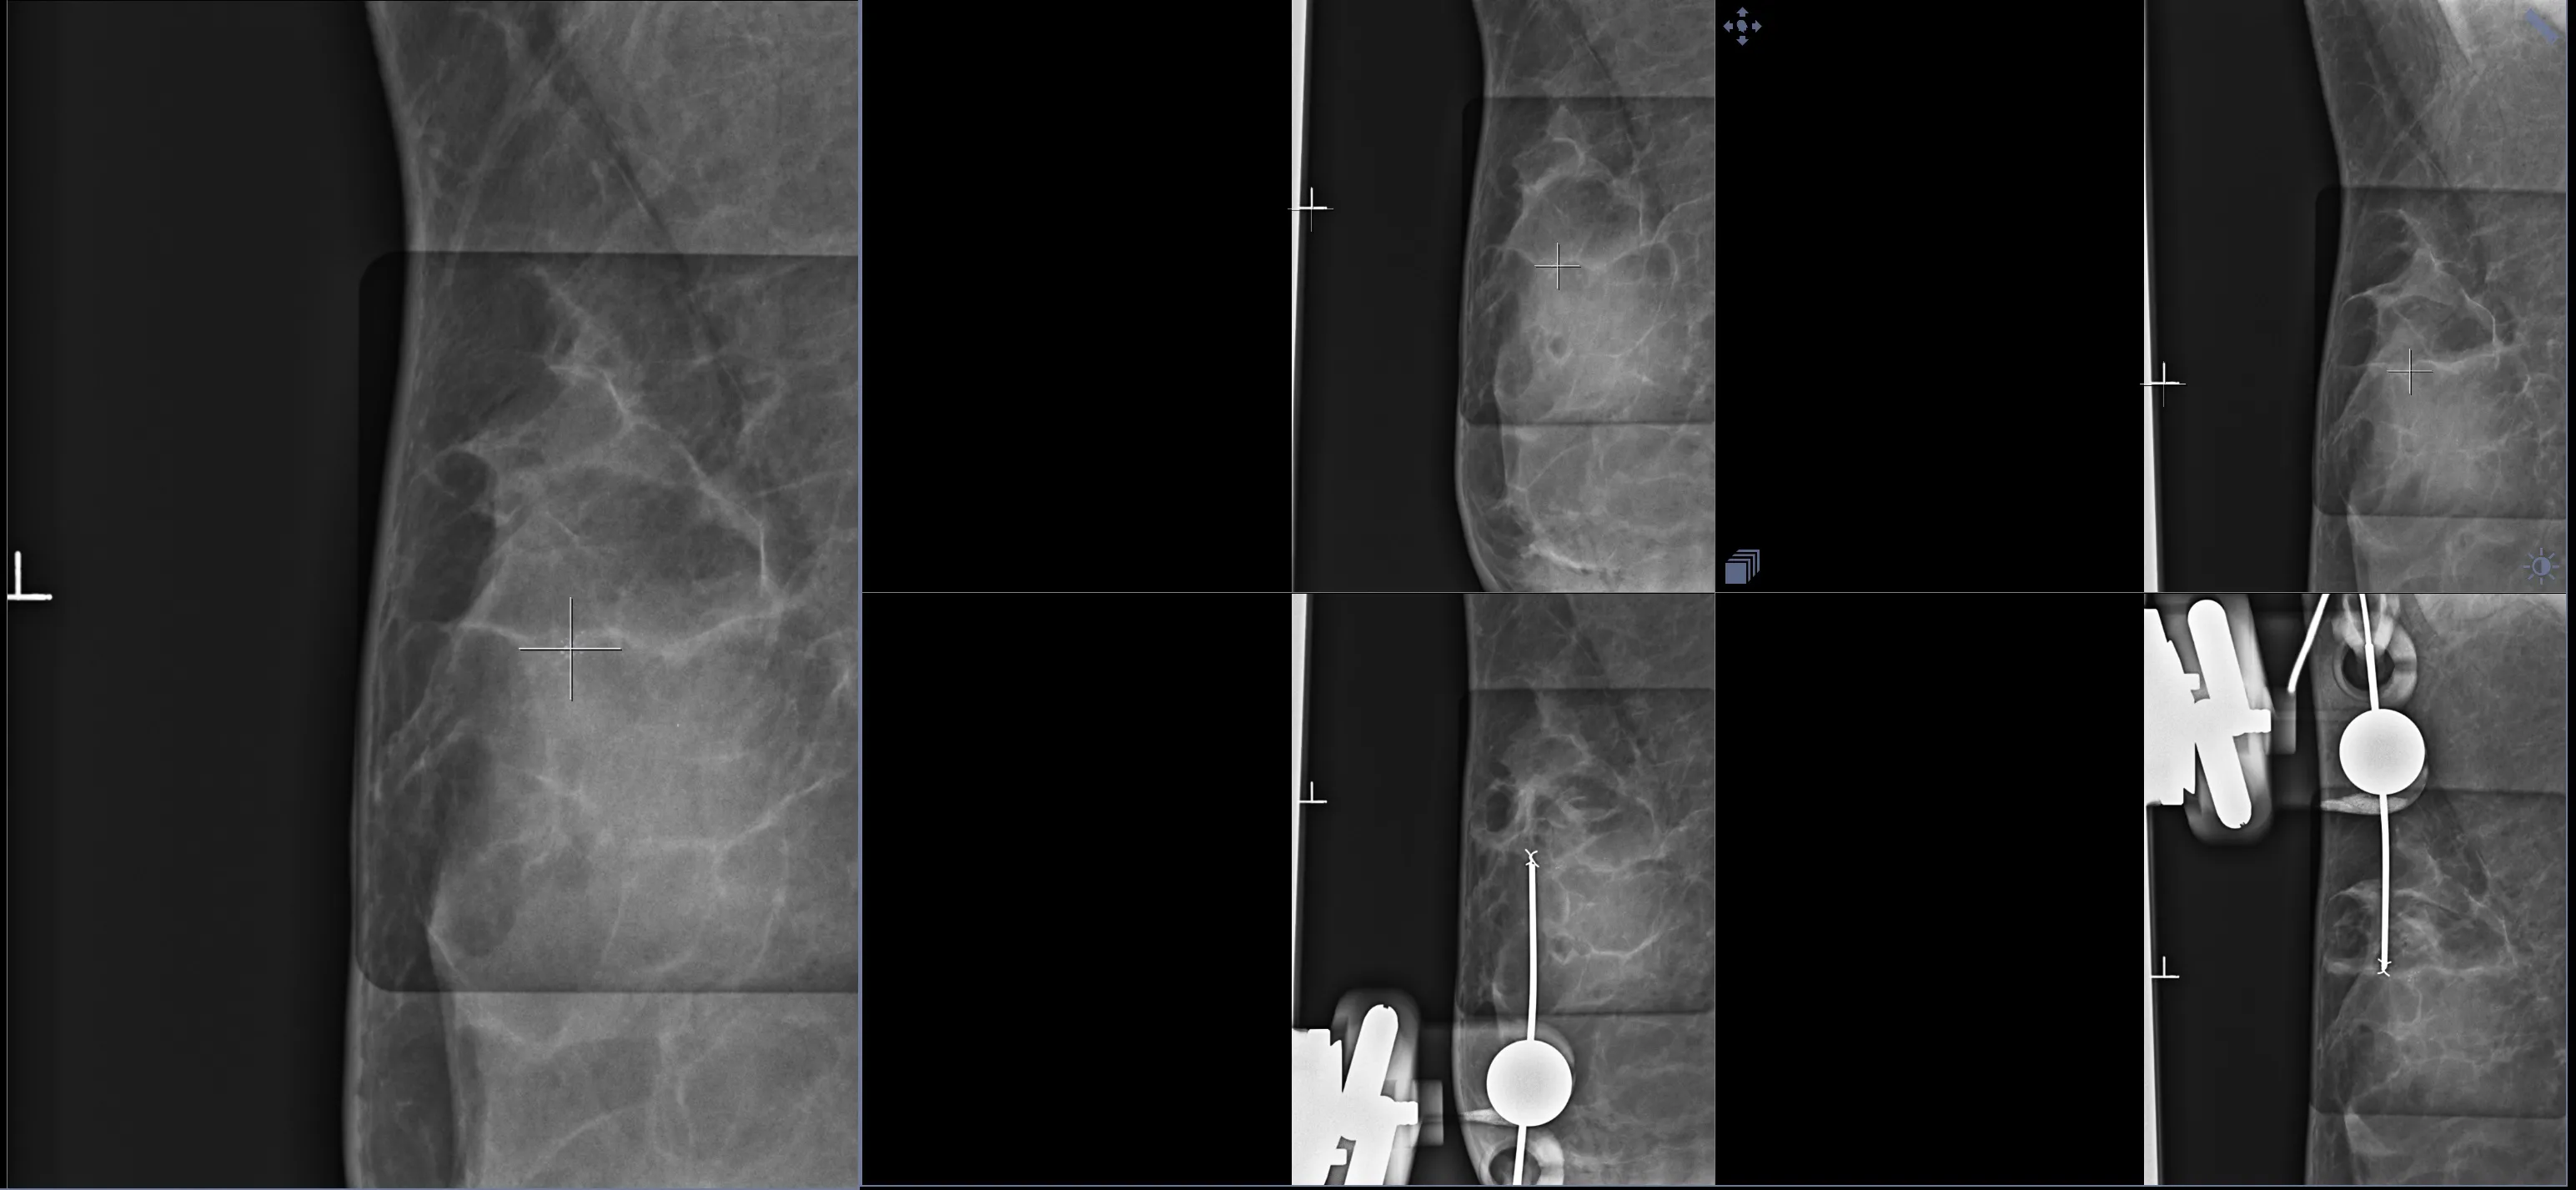

Ранее, во времена радикального, но не онкопластического подхода при лечении рака молочной железы, в таких случаях выполняли мастэктомию. Этой пациентке врач-маммолог, онкопластический хирург Оксана Васильевна Шулига-Недайхлебова первым этапом лечения предложила плановое оперативное вмешательство в объеме онкопластической лампэктомии правой МЗ с интраоперационным гистологическим исследованием чистоты краев резекции, биопсией сторожевых лимфоузлов. Учитывая специфичность образования, на предоперационном этапе breast-радиологом была установлена метка-локалайзер (фото) в участок микрокальцинатов под контролем маммографии.

Интраоперационно был выполнен рентгенконтроль удаленного сектора МЗ. Рентгенография интраоперационного материала установила, что патологически измененная ткань полностью удалена. Но в целях двойного и надежного контроля материал также отправлен на срочное (экспресс) морфологическое исследование чистоты краев резекции после цветовой маркировки. В заключении интраоперационного гистологического исследования рентгенологически данные радикального удаления опухоли подтверждены. Проведено дополнительное иссечение краев резекции и отправлено на экспресс морфологическое исследование – пока не получен результат чистых краев резекции дважды.